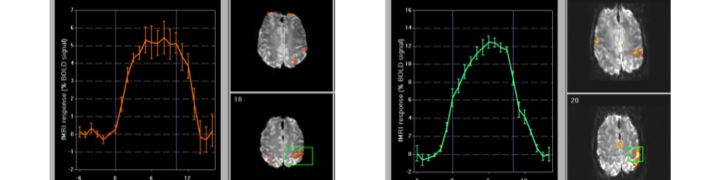

- MR spectroscopy and imaging

- Introduction to MR spectroscopy